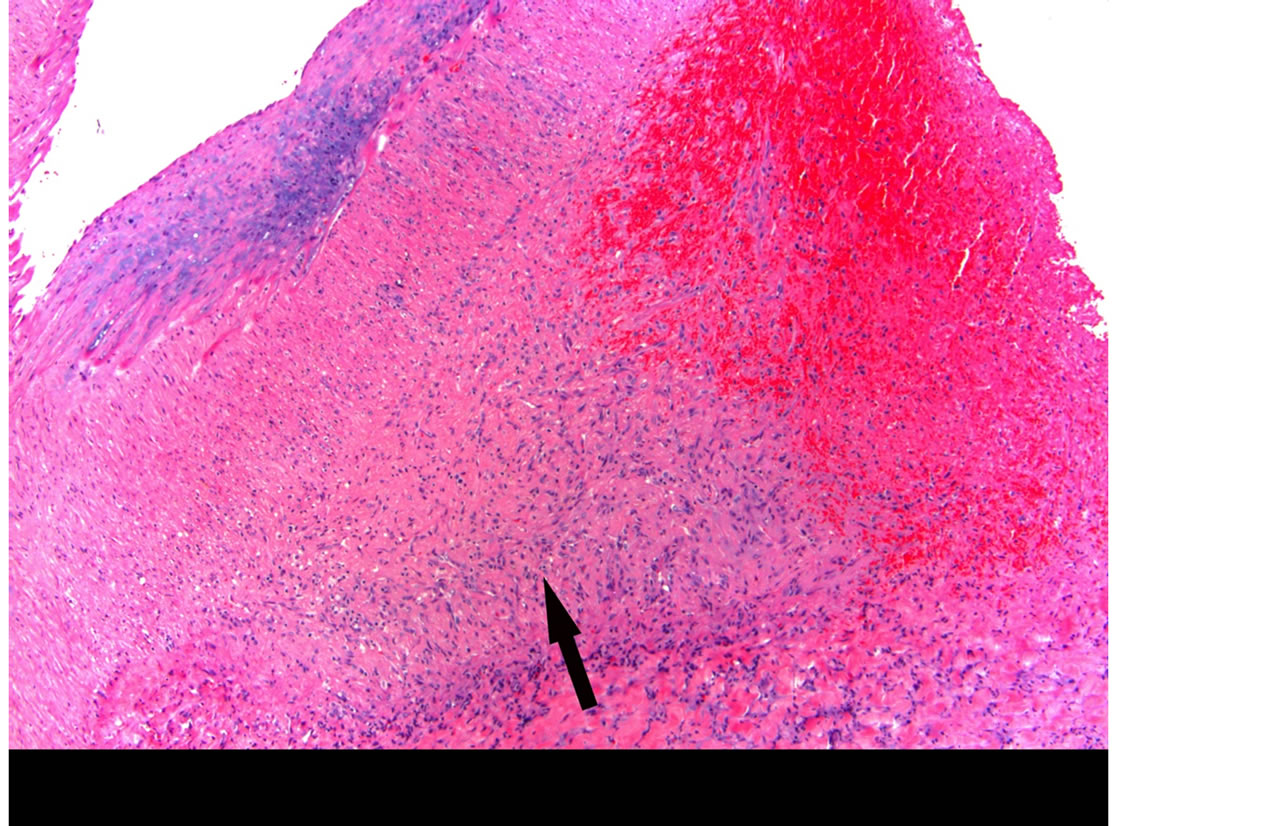

Focal areas of acute hemorrhage are evident in granulation tissue developed between the outer media and adventitia (Figure 10) that extends into a dissecting hematoma formed between the outer medial wall and the adventitia of a branching hilar artery (Figure 11). The medial wall bordering the pseudolumen shows patchy fibroblastic replacement of lost smooth muscle cells with collagen formation. A thick intimal plaque composed of mature granulation tissue overrides areas of medial repair to significantly narrow the true arterial lumen.

Figure 11. Reparative phase of segmental arterial mediolysis showing a dissecting hematoma developed between the outer media and adventitia. Arrow indicates an area of bleeding in recent granulation tissue in the pseudo lumen. Outer medial wall facing the dissection is fibrotic (yellow). A plaque of granulation tissue narrows the true lumen. Movat stain ×15.

The histological and angiographic findings and clinical symptoms in the current case are a classic representation of reparative phase SAM converted to FMD. An assortment of arterial lesions detected both histologically and radiologically is an important diagnostic feature of both injurious and reparative phase SAM. This variety is created by the varying intensities of the two different arterial injurious lesions, their asynchronous maturation, degree and sites of florid repair and segmental distribution [3]. This case illustrates the varying types of lesions typifying reparative phase SAM. These are medial-adventitial tears repaired by granulation tissue that serves as both sites and sources of dissecting and mural hematomas (Figures 8-10). Prior studies of SAM have shown that these lesions are initiated from hemorrhage in the granulation tissue filling the adventitial-medial separation plane rather than from intimal tears [1,3] and as this case illustrates, by the unsatisfactory stent attempt, this bleeding can be traumatically induced. We suspect that the cuff surrounding the celiac axis (Figure 1) represents a mural hematoma possibly partially or totally filled with granulation tissue. The second lesion is sequela aneurysms that are well repaired by granulation tissue that forms plaques over adjacent intact arterial intima and may bedeck surviving medial islands (Figure 8). These frequently grossly appear as large fusiform aneurysms (Figure 2) formed by two or more adjacent microscopic aneurysms created by the segmental distribution of SAM’s gaps. The latter fashions the saw-toothed appearance frequently found in medial FMD. The third lesion is the occurrence of medial granulation tissue with fibrosis repairing areas of mediolysis Figures 9 and 11). This change always commences in the outer media and may extend inwardly to involve some or all of the inner media. It is often patchy because of the survival of muscle cells in zones of mediolysis. Arterial stenosis, the forth lesion, is cause by the aforementioned lesions and reparative intimal plaques (Figures 3, 5 and 11). The fifth lesion is the formation of thrombi formed in both the aneurysms and pseudo-lumens of dissecting hematomas with thrombo-embolization developing distal to these lesions.